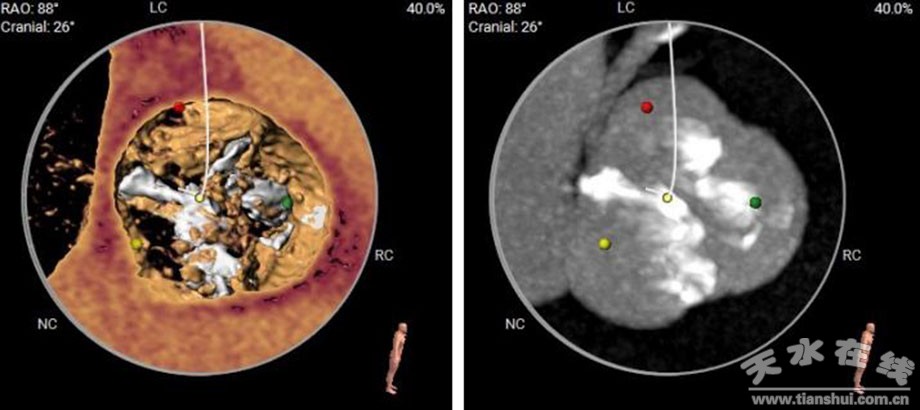

開(kāi)展TAVR手術(shù),精細(xì)的術(shù)前評(píng)估及MDT會(huì)診是至關(guān)重要的。在醫(yī)務(wù)科的大力協(xié)助下,洪志斌院長(zhǎng)組織心內(nèi)科、心外科、超聲科、麻醉科以及導(dǎo)管室和護(hù)理團(tuán)隊(duì),對(duì)王奶奶的病情及解剖結(jié)構(gòu)做了深入分析。心臟增強(qiáng)CT顯示,王奶奶的主動(dòng)脈瓣為Type1型的二葉瓣,左冠竇和右冠竇有非常嚴(yán)重的粘連,且各竇均有嚴(yán)重的鈣化,導(dǎo)致主動(dòng)脈瓣開(kāi)啟困難且閉合不佳。對(duì)主動(dòng)脈全程做分析,血管迂曲不嚴(yán)重,內(nèi)徑大小合適,冠脈開(kāi)口較高,整體解剖結(jié)構(gòu)非常適合TAVR手術(shù)。遂決定,盡快為王奶奶完成TAVR手術(shù),并邀請(qǐng)?zhí)m州大學(xué)第一醫(yī)院白明院長(zhǎng)及徐吉喆教授團(tuán)隊(duì)現(xiàn)場(chǎng)指導(dǎo)。

(CT影像下狹窄的主動(dòng)脈瓣)

(術(shù)中手術(shù)影像)